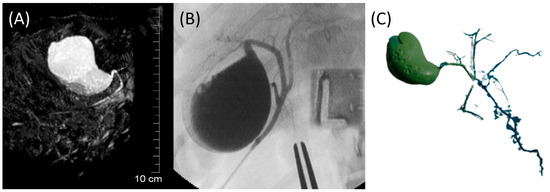

The GB (fundus, body, and neck), cystic duct, and CBD (at papilla and at extrahepatic ducts’ junction) were visible in MRCP, FRCP, and corrosion casting in all eight dogs. Visual comparisons between MRCP, FRCP and corrosion casting in Dog 6 with no evidence of disorders and Dog 8 with biliary disorders are shown in Figure 2 and Figure 3, respectively. The extrahepatic ducts and pancreatic ducts were variably visible in the MRCP and FRCP images. This did not allow for statistical analysis, only descriptive assessment.

Figure 2. Images of Dog 6 with no evidence of biliary and pancreatic disorders. (A) 3D-TSE-MRCP image showing normal gallbladder, cystic duct, and common bile duct. (B) FRCP image demonstrating normal biliary tract filled with contrast material. (C) Corrosion cast demonstrating normal biliary tract.